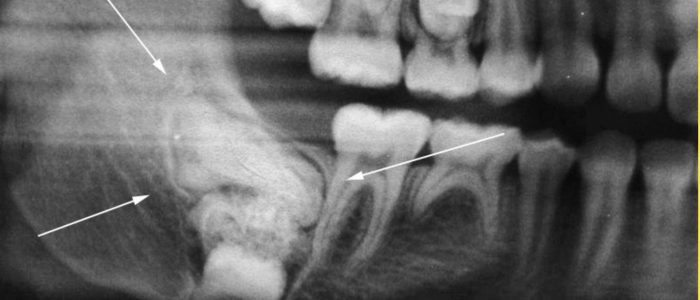

Как показывает практика, лучевая терапия остается бессильна в борьбе с фибромой челюсти. Поэтому из возможных вариантов лечения эффективен только один — хирургическое удаление. Прежде чем начинать лечение данного заболевания необходимо точно поставить диагноз. С целью диагностики фибромы челюсти врач отправит пройти рентгенологическое и микроскопическое исследование. Но убедиться в правильной дифференциации заболевания поможет только анализ на гистологию. Если подтверждается, что фиброма доброкачественная, проводится вылущивание опухоли вместе с капсулой. В случае со злокачественным образованием — иссечения значительного участка челюсти не избежать.